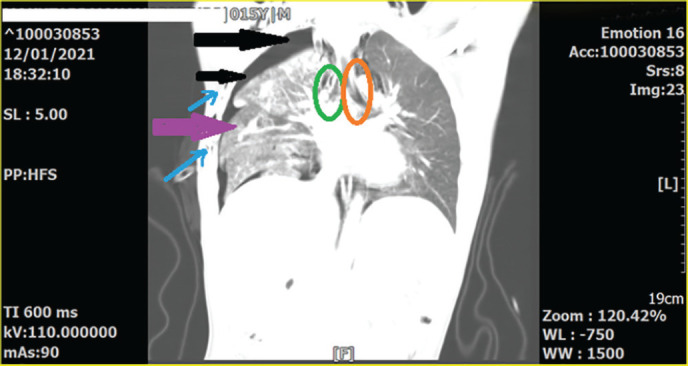

Bronchial rupture following major blunt chest trauma should be suspected in any case of massive and persistent air leak through the intercostal drain tube. Chest radiographs and chest computed tomography scans (CT scans) are highly suggestive of this extremely rare tracheobronchial injury. The present study reported a patient who was a 15-year-old boy. He was a case of a motor-car accident and was brought to the emergency room (ER) of Rajaie Hospital ( Shiraz, Iran) due to dyspnea and chest pain. The physical examination revealed a few crash injuries on his upper extremities, as well as subcutaneous emphysema in his neck. The chest X-ray revealed a right clavicular fracture, multiple rib fractures, a right pneumothorax (but no complete collapse or fallen lung), and also pneumo-mediastinum and subcutaneous emphysema. The chest CT revealed severe pulmonary contusion, severe right-sided pneumothorax, significant pneumo-mediastinum, subcutaneous emphysema, multiple right-side rib fractures, and mild displacement of the right main bronchus. Furthermore, no definitive signs of bronchial rupture were detected. Using a mechanical ventilator, the following parameters were revealed. The maximum pressure (Pmax)=7cm, H2o (was very low), plateau pressure (P. Plateau), and expiratory tidal volume (TV) were not detected due to insufficient amounts. Additionally, increasing TV did not change those values. Bronchial rupture is one of the most important and serious differential diagnoses in forceful chest traumas when the mechanical ventilator reveals low Pmax, very low P.platue, and expiratory TV, with no change in those values with increasing TV.